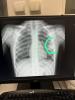

Я то спасла свою дочь от дальнейших последствий,мне жалко матерей которые поверят этому «Врачу» и поедут домой!

Которые будут искать причину плохого состояния:рвоты ,температуры,боли в легких где-то в инфекционной,у невролога!

А в это время лёгкие будут повреждаться и дальше!!!!

Болезнь эта-это вам не шутки ,она сразу повреждает плевру ,сразу появляется жидкость!!!!!

Мне жалко,что сразу не назначается нужное лечение ,тогда как за это время можно было бы избежать многих последствий! Вот и всё!

@mylkiway, Ребенка с пневмонией отправили домой,сказав,что б попили магний.Иъ причин яцахь сунам ца хаа)